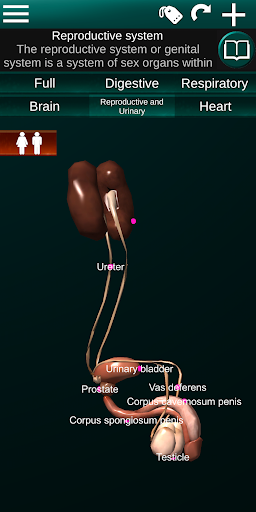

* Sistem reproduksi, yang meliputi organ reproduksi pria dan wanita.

* Bandingkan organ pria dan wanita.